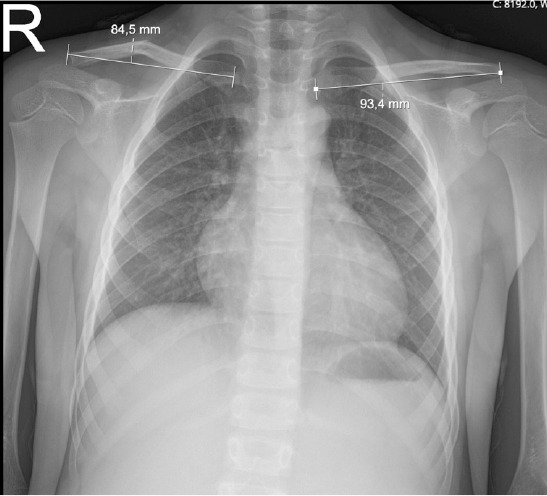

Methods: Patients were divided into two groups based on the preferred conservative management method: Group 1 (arm sling) and Group 2 (figure-of-eight bandage). The degree of angulation and shortening was measured at initial admission and during follow-up. Demographic characteristics and radiological data were compared between the two groups.

Results: Group 1 included 10 girls and 10 boys, while Group 2 included 12 girls and 17 boys (p=0.761). The mean shortening at initial presentation was 7.28+-6.06 mm in Group 1 and 6.65+-5.58 mm in Group 2 (p=0.625). At follow-up, the mean shortening was 6.24+-5.59 mm in Group 1 and 5.59+-4.91 mm in Group 2 (p=0.569). The mean angulation at initial presentation was 21.28+-10.05° in Group 1 and 20.41+-12.23° in Group 2 (p=0.752). At follow-up, the mean angulation was 14.45+-9.41° in Group 1 and 11.82+-10.27° in Group 2 (p=0.189). In intra-group comparisons, no significant difference was found between the initial shortening and follow-up shortening in either group (Group 1: p=0.062; Group 2: p=0.190). A significant reduction in angulation was observed in both groups during follow-up (p=0.001 for Group 1; p=0.001 for Group 2).